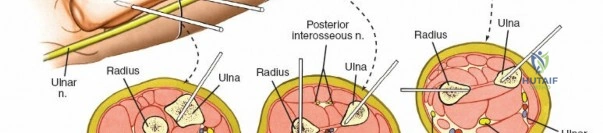

* Proximal Third: The posterior interosseous nerve (PIN) courses through the supinator muscle. Pin placement in the proximal radius is highly hazardous and generally avoided unless absolutely necessary. If required, a formal dorsal approach (Thompson) is used to visualize and protect the PIN.

* Middle Third: Pins can be placed dorsolaterally. The superficial radial nerve (SRN) and cephalic vein must be protected.

Mid-to-Proximal Radius Pin Placement

1. Supinate the forearm to move the PIN dorsally and radially.

2. Make an incision over the dorsolateral aspect of the radius.

3. Dissect between the extensor carpi radialis brevis (ECRB) and the extensor digitorum communis (EDC).

4. Use retractors to carefully protect the PIN.

5. Insert the tissue sleeve, pre-drill, and place a 4.0 mm pin bicortically.

Ulna External Fixation

The ulna is straightforward due to its subcutaneous border.

- Palpate the subcutaneous crest of the ulna.

- Make stab incisions over the planned pin sites (typically two proximal and two distal to the fracture).

- Dissect bluntly to the periosteum.

- Place the tissue sleeve and drill perpendicular to the longitudinal axis of the bone.

- Insert 4.0 mm pins bicortically.

- Connect the pins with an 8 mm rod and reduce the fracture.